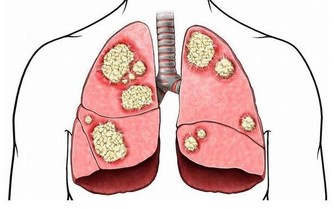

(2)皮膚發紅:肺結核

皮膚發紅是由於毛細血管擴張充血、血流加速以及紅細胞數量增多所致,在生理情況下見於運動、飲酒時。

疾病情況下見於發熱性疾病,如大葉性肺炎、肺結核、猩紅熱等,以及某些中毒,如阿托品等藥物中毒;紅細胞數量增多,如真性紅細胞增多症等也可引起皮膚發紅。